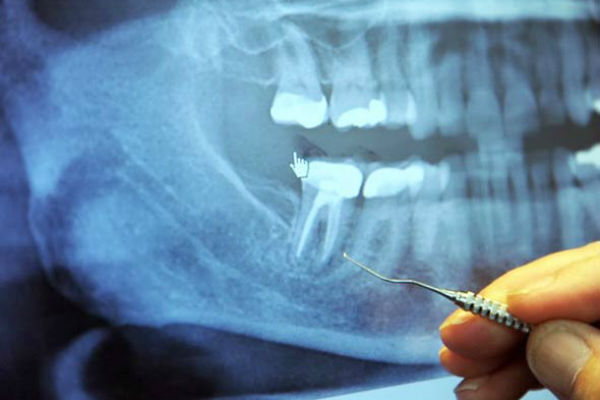

Upitanju je vađenje živca. Na milione ovih operacija provesti svake godine.

U sredini svakog zuba nalazi se zubna šupljina iu njoj pulpa, koja povezuje krvne žile i živce. Oko zubne šupljine se nalazi dentin, koji je sačinjen od živih stanica koje luče tvrdu mineralnu supstancu. Vanjski dio zuba naziva se enamel i on okružuje dentin.

Korijeni svakog zuba dopiru do vilice i ostaju na svom mjestu zahvaljujući peridontalnom ligamentu. Stomatolog u školi uče da svaki zub ima 1-4 veća kanala. Međutim, postoji gomila kanala koja se uopće ne spominje.

Svaki zub ima čitav labirint sitnih cjevčica koje bi, kad bi se razmotale, bile dužine oko nekoliko kilometara. Weston Price je identificirao 75 odvojenih pristupnih kanala u jednom središnjem sjekutiću.

Mikroskopski organizmi se redovito kreću u i oko ovih cjevčica kao krtice u podzemnim tunelima.

Kad zubar izvede operaciju vađenja živaca, on probuši zub, a zatim ispuni šupljinu supstancom koja odsijeca dotok krvi do zuba, tako da ona više ne može cirkulira kroz zub. Međutim, labirint cjevčica i dalje ostaje tamo, a bakterije, koje više nemaju svoj izvor hrane, kriju se u ovim tunelima gdje su sigurne od antibiotika i imune obrane organizma.